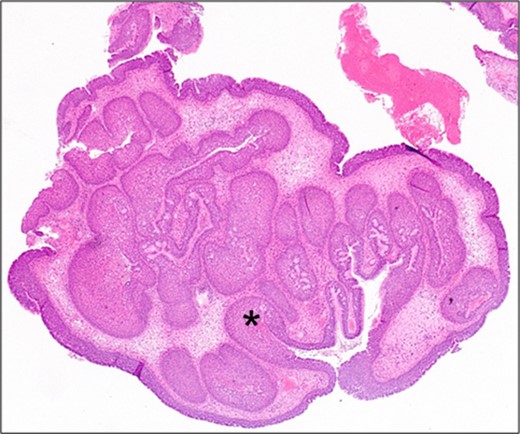

A transnasal endoscopic resection of the right sinonasal tumour was planned. Intraoperative frozen sections showed papillomatous and squamous features consistent with inverted papilloma. The operative findings showed the tumour to be originating from a bony prominence over the postero-lateral wall of the maxillary antrum which was drilled down at the end of the procedure to reduce risk of recurrence. Full macroscopic clearance of the tumour was achieved. The diagnosis of IP was subsequently confirmed on paraffin embedded histological assessment (Fig. 3). No adjuvant therapy was given, and the patient is currently 12 months post-surgery with no endoscopic signs of disease recurrence. Expression of p16 protein which is associated with human papillomavirus status, was negative in this patient.

Medium power photomicrograph showing benign proliferative papillomatous type lesion with oedematous stroma and inflammation. There is invagination of the epithelium into the stroma (black asterisk) (H&E; ×20).